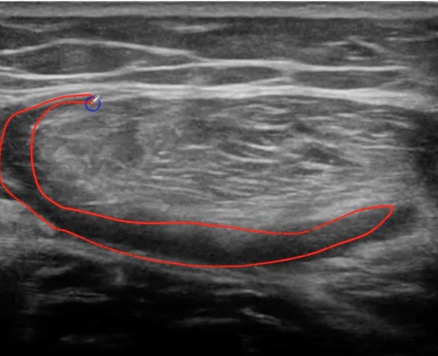

El corte transversal es elprimer corte que debes hacer, te va a permitir ubicarte en el espacio e identificar con mayor rapidez al recto anterior. Su arquitectura es un tanto atípica.

El recto anterior tiene un septo central en forma de S (azul). Las roturas musculares del recto anterior, son frecuentes próximas al septo (aunque tambión podemos encontrarnos roturas miofasciales que tambien te enseñaremos).

El contorno de la sección transversal del recto anterior queda delimitada por el contorno (verde).